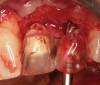

A 53-year-old woman presented with a failing implant in the No. 7 site (Figure 12 and Figure 13). Her desire was to eliminate infection and preserve esthetics. A team effort between the periodontist and restorative dentist to advocate for additional restorative dentistry as well as manage the patient’s expectation of time required was essential. In addition, the patient needed to have realistic expectations of a compromised outcome. Both the restorative dentist and the periodontist informed the patient about the difficulty of achieving this with acceptable esthetic results. Mutual emotional and technical support was required to successfully complete this case, from initial grafting of the defect to placement of anterior restorations (Figure 14 through Figure 23).